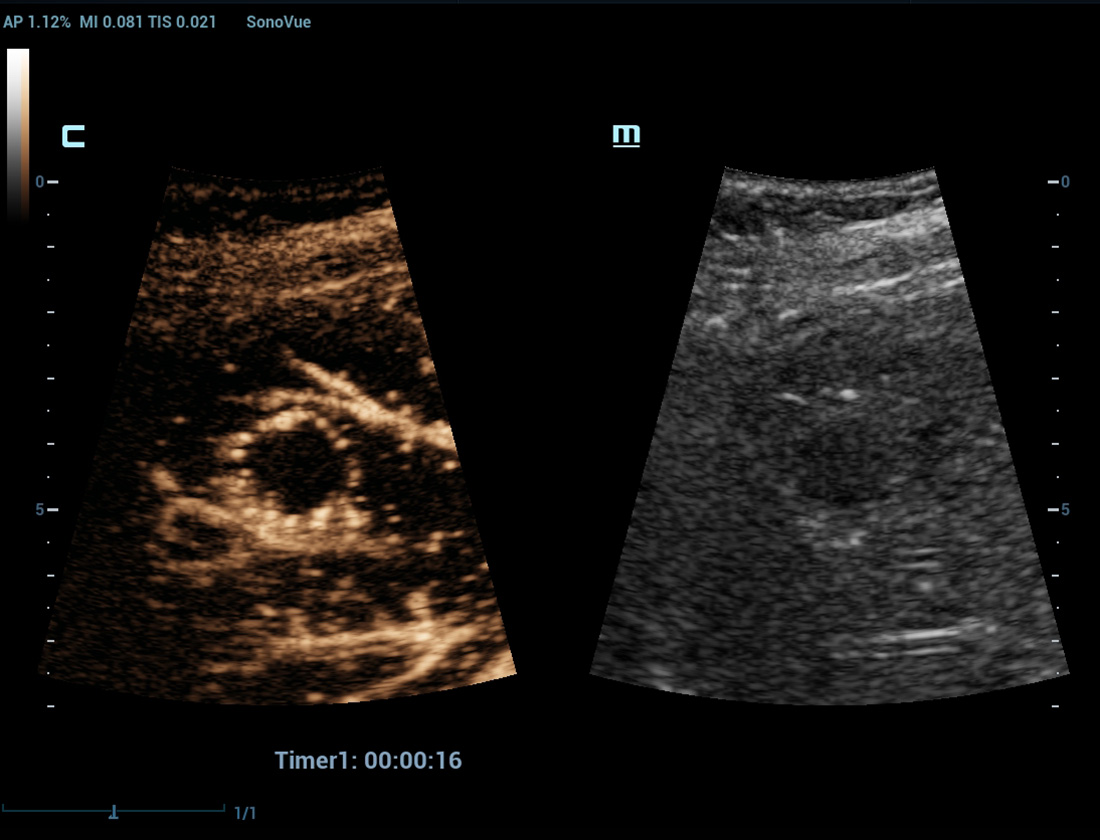

CEUS avan?ado

UWN+ (Ultra-Wideband Non-Linear) CEUS

CEUS ã Tumor maligno de mama

Ao utilizar tanto a segunda harm?nica quanto os sinais fundamentais n?o lineares, o UWN+ permite alta sensibilidade dos sinais das bolhas e maior dura??o de perfus?o com baixo MI, auxiliando nas avalia??es de tumores.

Avalia??o apû°s abla??o

Imagem de contraste UWN+

Detecta e utiliza os sinais fundamentais n?o lineares e os de segunda harm?nica, gerando imagens com melhorias significativas:

- Excelente sensibilidade do agente, mesmo com sinal fraco

- Tempo de perfus?o mais longo com menor IM

- Melhor visualiza??o da perfus?o de pequenos vasos com MFE (Micro Flow Enhancement)

CEUS ã Massa mamûÀria

CEUS ã Massa hepûÀtica